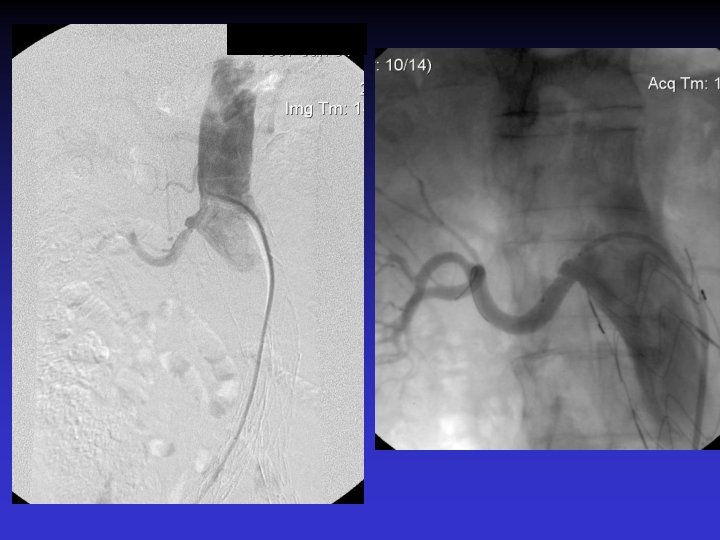

Case # 2 • 50 -year-old male with solitary kidney. • Smoker. • Refractory HTN. • Cr: 3. 8 mg/dl

• B/P: 160/80 mm. Hg • Cr: 1. 8 mg/dl

The patient was re-admitted 18 months later with Cr: 2. 8 mg/dl, and BP: 180/90 mm. Hg.